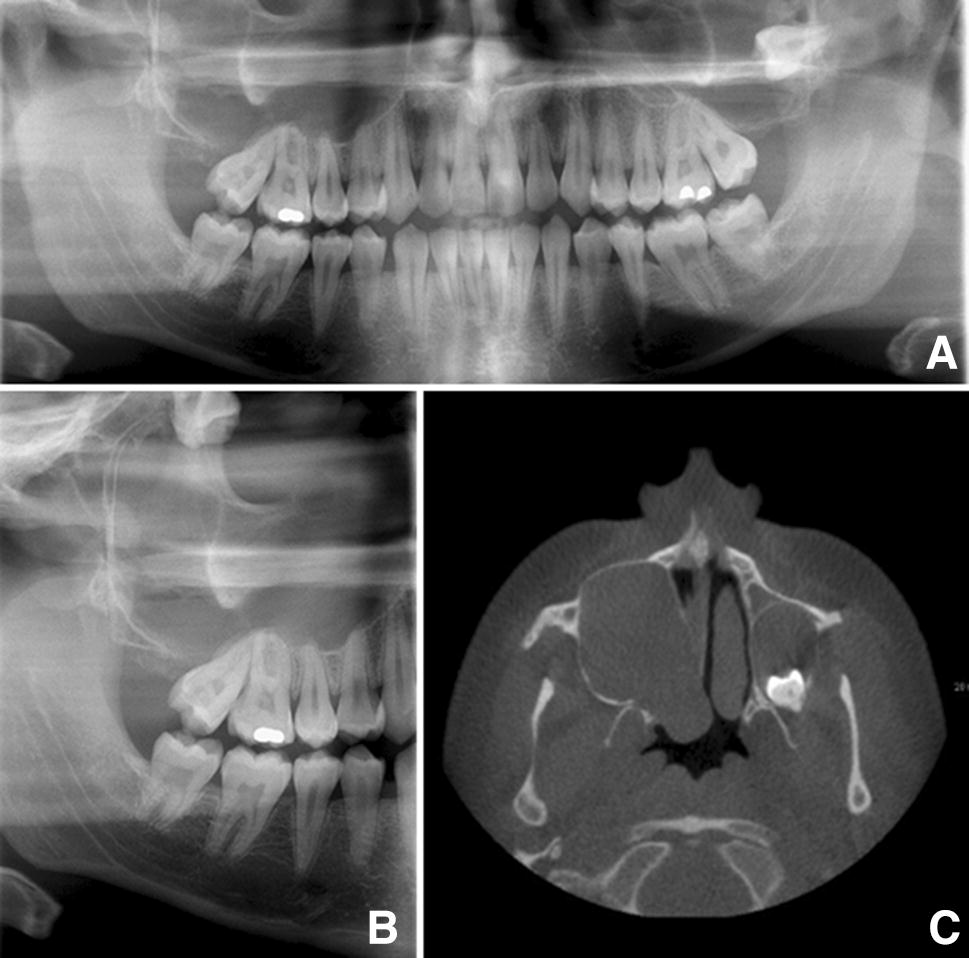

A 20-year male presented for extraction of a partially erupted and disto-angular positioned upper right second molar. On routine pre-operative radiographs, it was noted that both the left and right upper third molar teeth were impacted, displaced and associated with large, expansile radiolucencies (Fig. 3a, b). A Cone Beam CT (CBCT) revealed extensive expansion of both the right and left maxillary sinus by a soft tissue lesion (Fig. 3c), with the right lesion showing soft tissue extending up to the orbital floor. Both third molars had been displaced superiorly. The axial view (Fig. 3c) clearly shows the extensive medial and posterior expansion of the right maxillary sinus. The clinical differential diagnosis included OKC and dentigerous cyst.

Fig. 3

a Full OPT from case 2, showing the displaced upper left 8 (UL8) and associated radiolucency. Note that displaced upper right 8 (UR8) cannot be seen in this radiograph b Sectional OPT from case 2 showing displaced upper right 8 (UR8) with associated expansile radiolucency c CBCT from case 2 showing bilateral expansile lesions in the left and right maxilla

A review of OOCs showed that 93% of cases were unilocular [7] and this is reflected in the cases presented here, with only the lesions in the left maxilla and mandible of case 1 (Fig. 1) showing a multilocular appearance. The cases presented here showed marked expansion along with displaced, but not resorbed, teeth, which has been reported in the literature previously [8]. This may be a helpful feature when trying to differentiate these lesions from common odontogenic tumours, such as ameloblastoma, which often show resorption of teeth.